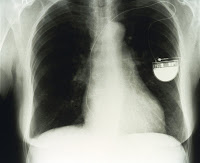

From this I have worked out how to progress. I researched into the artists of the welcome collection. The Images below are taken from the collection. I looked into the idea of aliments and illnesses. This is what i would like to represent in my final year project. I want to make things that usually repulse us, appealing and almost beautiful. The following three images are of illnesses (in order) Osteoporosis, X-ray of a pacemaker and a close up of a blot clot. They will be useful as ideas that I may transfer to etchings.